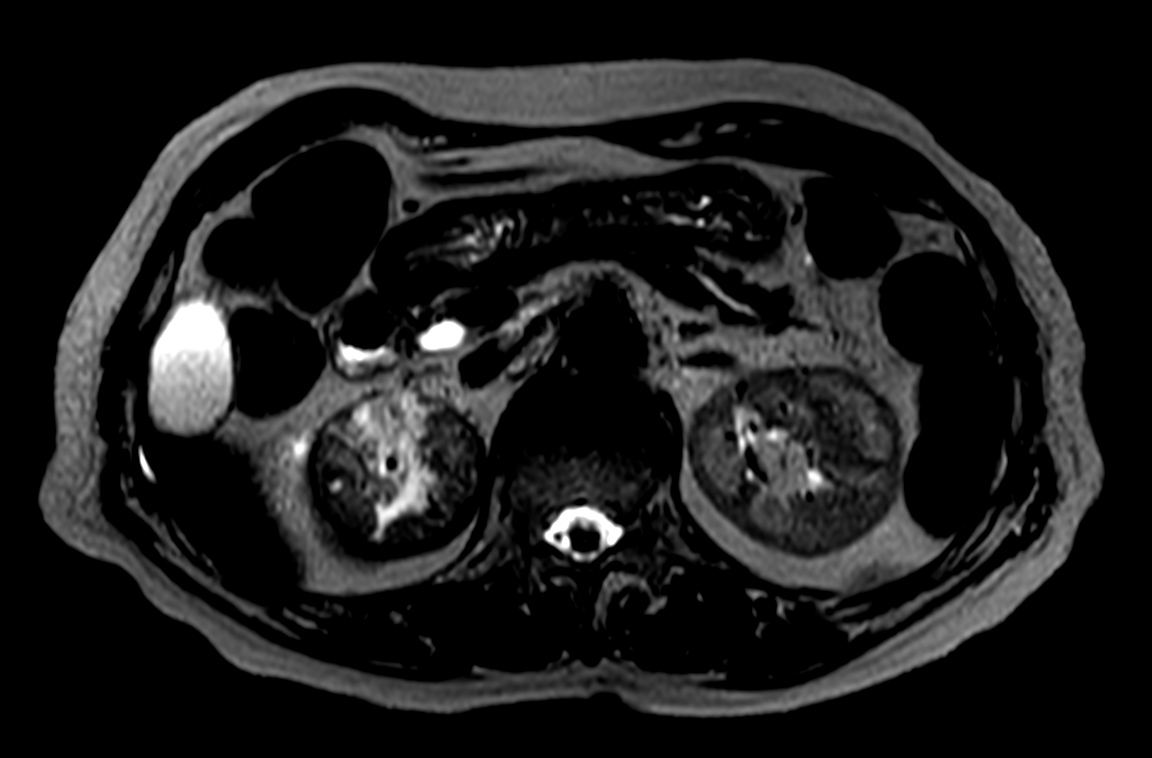

Patient with a kidney lesion. The ExamCard includes techniques for 3D imaging (PelvisVIEW, eTHRIVE) allowing for multiple image directions in one single scan, efficient fat-free imaging over large field-of-views (mDIXON XD), a multi-phase contrast-enhanced sequence (4D FreeBreathing) to improve imaging confidence and Compressed SENSE to accelerate the entire exam.

T1w mDIXON XD FFE (Water only)